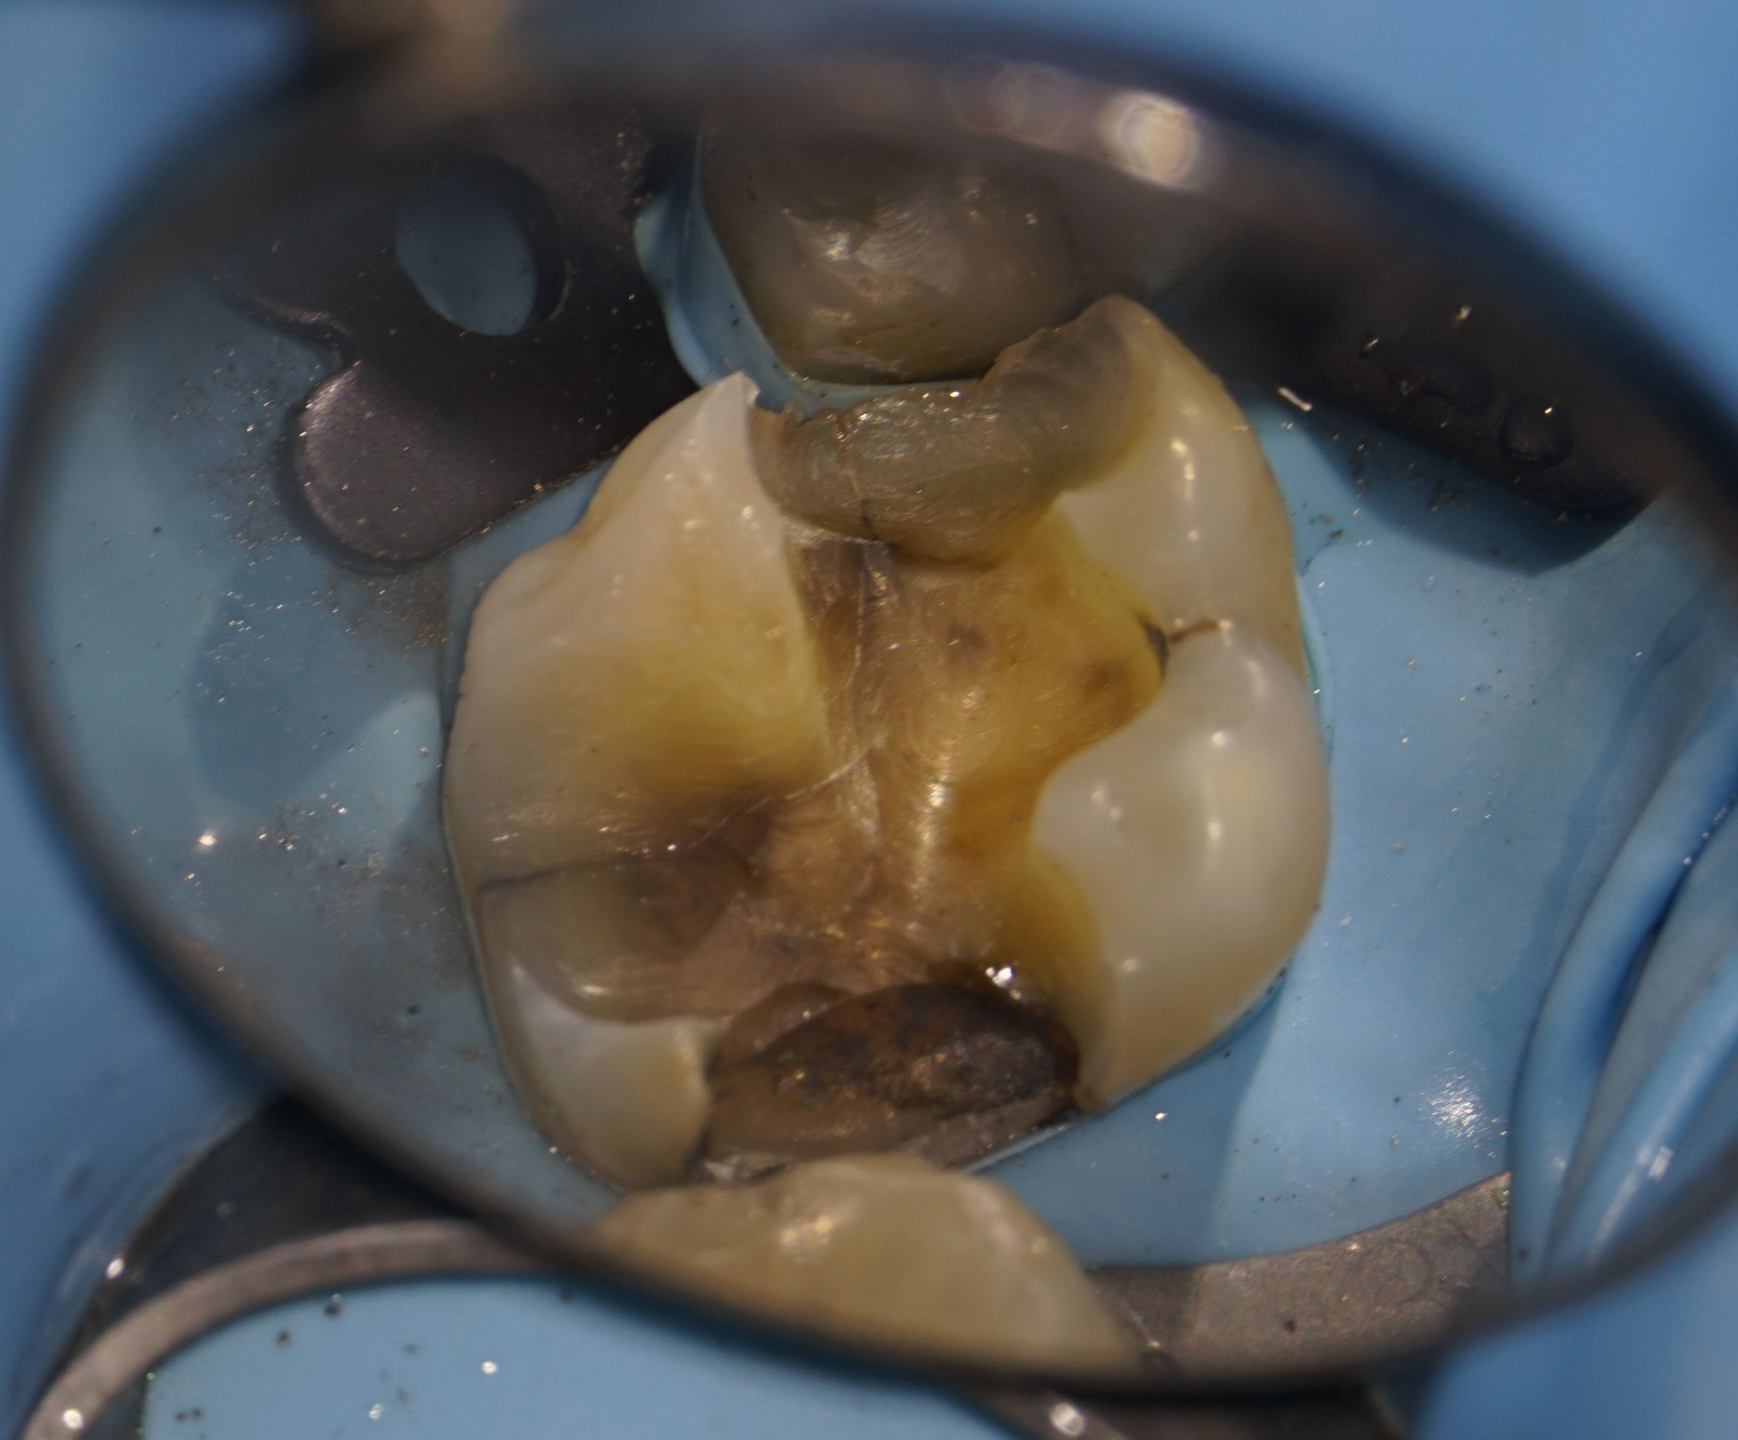

Ekskavering

Hvor og hvor meget du skal fjerne?

Hvor og hvor meget kan du efterlade?

Hvordan?

Caries Ekskavering

Dentin er ikke bare dentin!

Dentin er et komplekst væv at bonde til. Det er fugtigt og sejt, faktisk lidt bevægeligt.

For at skabe høj bindingsstyrke skal man forstå kvaliteten af den dentin der er til rådighed. Superficial dentin vil bonde anderledes end dyb dentin. Inficeret dentin vil variere i forhold til graden af infiltration.

Det kaldes;

"Hirachy Of Bondability"

Du vil lære at lægge et hierarkisk kort ud over kaviteten, så du kender dine forventelige bindingsstyrker og ved, hvor du skal være ekstra påpasselig.

Infraktioner

Infraktioner har altid voldt mig hovedbrud. Hvad stiller jeg op med dem? Efter at have gennemført Dr. David Allemans Mastership i Biomimetisk Tandbehandling er jeg ikke længere så meget i tvivl.

JEG DISSIKERER INFRAKTIONER DER LØBER IND I DENTINEN.

Hvorfor? Fordi det giver helt vildt god mening. Er der evidens for det? Formentlig ikke endnu. Det er lidt ligesom med bidfunktion. Der er ikke enighed og derfor stor forvirring.

Jeg træffer valget at dissikere revner og forebygge yderligere vandring, og jeg udfører det med modig, velovervejet hånd. Det er i princippet det samme, som ingeniører gør ved revner i fly vinger.